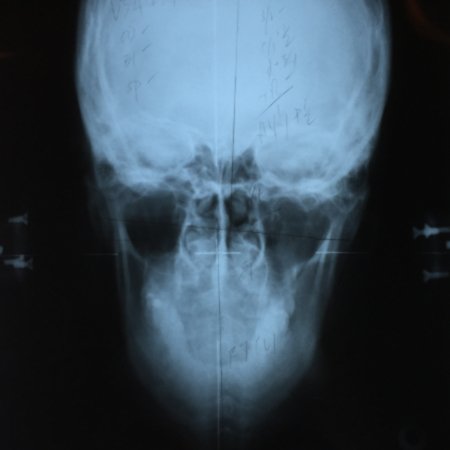

If it’s your first time to go to an upper cervical chiropractor, you’ll need an average of 8 to 12 visits, then the doctor will re-assess you for lifetime treatment. The first session involves a general assessment of your health, habits, and posture, followed by three x-rays (from the side, front, and top of head and neck) specific to the practice of upper cervical chiropractic. This is usually the longest session. The doctor will then study your x-rays, posture, and result of the initial consultation, and based on all these will determine if you need an atlas or spine adjustment on your next visit.